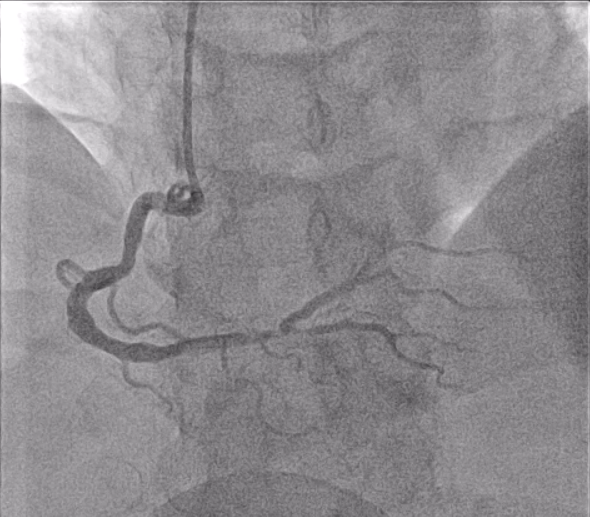

ECG showed normal sinus rhythm with ST elevation in II, III and AvF. Complete blood count, electrolytes and kidney function were within normal limits. Troponin-t was not available before catheterization. Coronary angiogram through a right radial approach showed single vessel disease with a diffuse critical stenosis at the distal RCA bifurcation (Medina 1,1,0) with a severe size mismatch between the distal RCA and RPDA.

Intracoronary GTN was given after predilatation. IVUS showed mostly fibrous plaque with plaque extending from the distal RCA to the proximal RPDA. Reference diameters (EEL) were 4.5mm proximally in the distal RCA and 2.75mm distally in the RPDA. PCI to the distal RCA to RPDA with a provisional approach, using a stent with high postdilatation limits across the bifurcation.

PCI was performed with a 7Fr JR4 Guide with wires in the RPDA and RPL. Lesion was predilated and stented with a 2.75x33m DES and postdilated with a 4.5mm NC proximal to the RCA bifurcation. IVUS showed underexpansion distally and severe malapposition proximally hence the stent was further postdilated with 2.75mm NC distally and 4.5mm in the distal RCA. ClearStent showed unravelling of the stent, which was confirmed on IVUS with a new total stent length of 52mm. The distal RCA diameter had grown in size to 5mm at the site of the proximal stent edge. A 4.5x24mm DES was implanted in the distal RCA to cover the unravelled stent struts, which was postdilated with a 5mm NC balloon. Final IVUS showed the stent to have adequate apposition with no immediate complications.